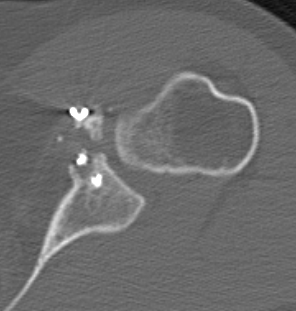

Case 2: Large glenoid defect